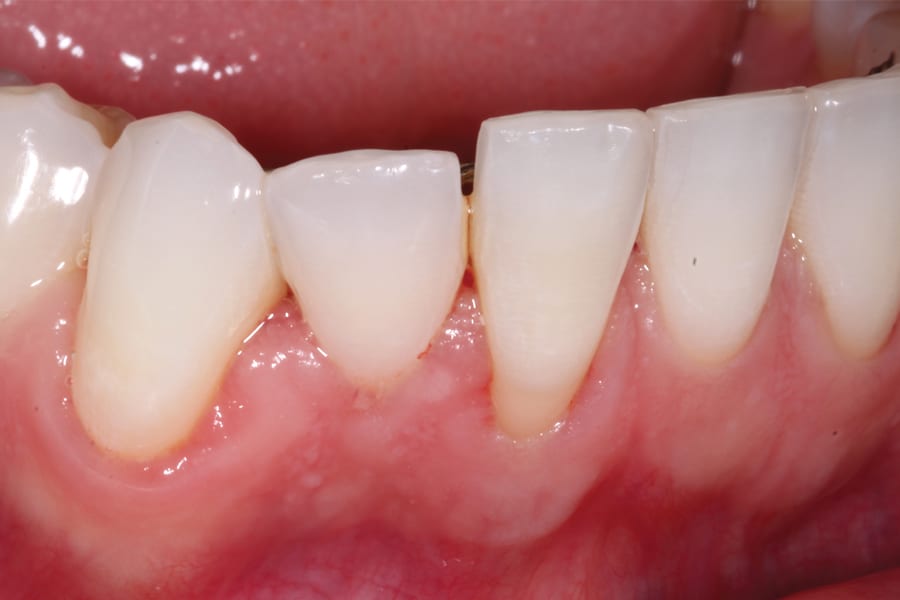

There are, however, some unfavorable long-term ramifications of this design. Due to the nature of stainless steel, which has memory and over time will partially return to its original shape, these twisted lingual retainers may "unwind" or uncoil and exert unintended forces on the teeth to which they are bonded (Figure 5 and Figure 6, Figure 8 through Figure 11, Figure 14 through Figure 16). This leads to excessive labial or lingual root torquing movements, often resulting in highly undesirable recessions, dehiscences, and fenestrations. Because it may take years for this occurrence to manifest, the orthodontist (who usually places the retainer) is typically both unaware of the situation, as he or she does not customarily follow patients for such long-term periods, and free of blame. The periodontal implications of this outcome can be highly detrimental, as seen in the cases presented herein.

Although spontaneous improvement of the investing tissues is often observed through orthodontic correction (Figure 7 and Figure 13),5 additional corrective action is frequently indicated afterwards, particularly when cosmetics are to be considered. A recession defect case is depicted in Figure 17 through Figure 26 in which corrective action was necessary and accomplished through aligner therapy followed by connective tissue grafting.6 It should be noted that although this corrective scheme may successfully achieve an acceptable cosmetic and functional result, it is not likely a regenerative outcome in the sense that a previously dehisced root surface typically will not attain ligamentous insertion into freshly laid cementum. A long junctional epithelium or connective tissue attachment at best is the more likely outcome. Consequently, a preventive approach initially would be more desirable.